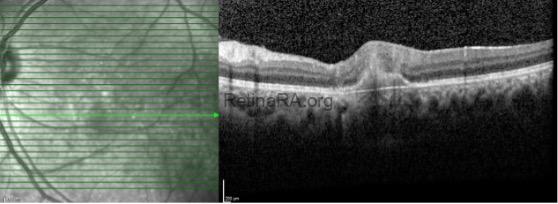

With the diagnosis of ocular toxoplasmosis, trimethoprim sulfamethoxazole with azithromycin and oral steroid treatments were started. In the 1st month control OCT imaging, scarring in the lesion and complete recovery of serous detachment were observed.

Ocular toxoplasmosis should also be considered in the differential diagnosis of serous retinal detachment. Serous retinal detachment accompanying the lesion is observed in 20-25% of toxoplasma cases, and this rate may increase even more with routine OCT imaging. Its distinguishing features are unilateral nature, typical retinochoroiditis focus and/or the presence of old scar.